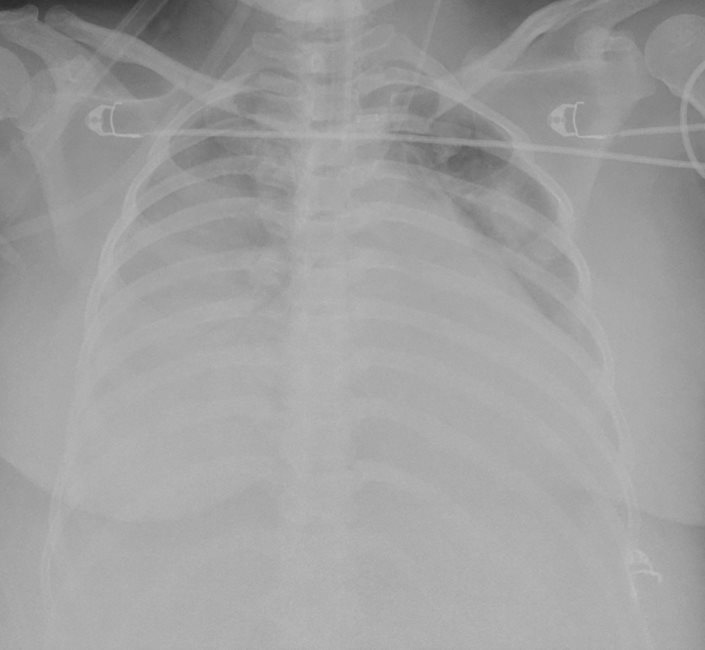

Nhận định về ca bệnh, ThS.BS. Giang Minh Nhật - Trưởng đơn vị Hồi sức tích cực tim mạch – Bệnh viện Nhân dân Gia Định cho biết : “Khi được chuyển đến bệnh viện Nhân dân Gia Định, tình trạng suy hô hấp của bệnh nhân diễn tiến nguy hiểm đến tính mạng (hội chứng nguy kịch hô hấp cấp) không đáp ứng thở máy xâm lấn, tổn thương phổi trên Xquang ngực chiếm hơn 80% thể tích phổi. Sản phụ P. được can thiệp VV-ECMO (oxy hoá máu màng ngoài cơ thể) cấp cứu vì suy hô hấp giảm oxy máu kháng trị. Sau can thiệp VV-ECMO và lọc máu liên tục 14 ngày, tình trạng suy hô hấp và tổn thương thận cấp của sản phụ P. hồi phục ngoạn mục, tổn thương gan, giảm tiểu cầu và tán huyết đều ổn định.